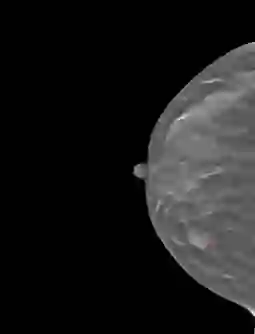

Accurately classifying malignancy of lesions detected in a screening scan plays a critical role in reducing false positives. Through extracting and analyzing a large numbers of quantitative image features, radiomics holds great potential to differentiate the malignant tumors from benign ones. Since not all radiomic features contribute to an effective classifying model, selecting an optimal feature subset is critical. This work proposes a new multi-objective based feature selection (MO-FS) algorithm that considers both sensitivity and specificity simultaneously as the objective functions during the feature selection. In MO-FS, we developed a modified entropy based termination criterion (METC) to stop the algorithm automatically rather than relying on a preset number of generations. We also designed a solution selection methodology for multi-objective learning using the evidential reasoning approach (SMOLER) to automatically select the optimal solution from the Pareto-optimal set. Furthermore, an adaptive mutation operation was developed to generate the mutation probability in MO-FS automatically. The MO-FS was evaluated for classifying lung nodule malignancy in low-dose CT and breast lesion malignancy in digital breast tomosynthesis. Compared with other commonly used feature selection methods, the experimental results for both lung nodule and breast lesion malignancy classification demonstrated that the feature set by selected MO-FS achieved better classification performance.